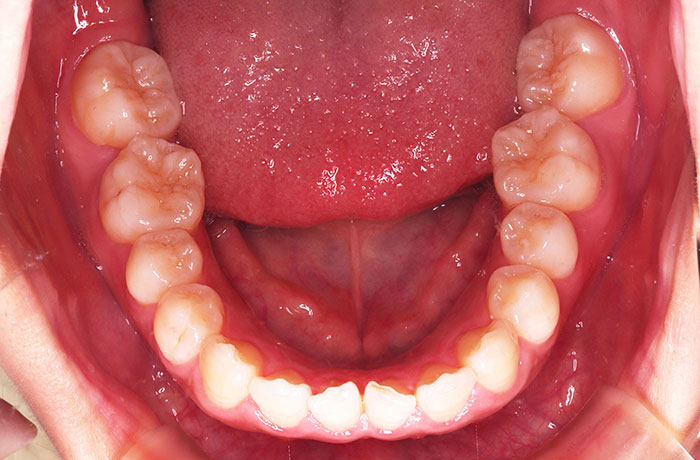

治療前

before

患者の症状 叢生、正中のずれ、上顎左右側切歯の口蓋側転位(交叉咬合)

治療方法 非抜歯で、マウスピース型カスタムメイド矯正歯科装置(インビザライン)による矯正

歯列弓を拡大することで非抜歯を可能にしました。

治療結果 側切歯の交叉咬合は解消、上下正中のずれも改善し咬み合わせが良くなりました。